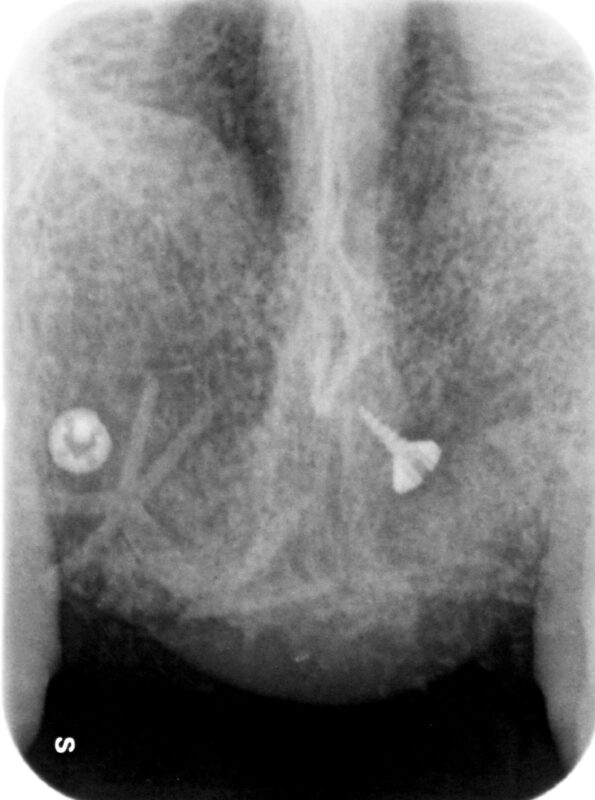

術前CT

サジタル(縦断面)

アキシャル(水平断面)

真ん中の黒い穴は切歯孔

複数のソフトで治療を検討しましたが、骨の厚みが3mm程度しかなく、インプラント治療行うには最低

8mm程度は欲しいため、インプラント埋伏オペ前にあらかじめ骨を作る処置を行いました。